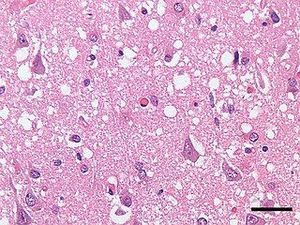

A prion is a misfolded protein that can transmit its misfolded shape onto normal variants of the same protein. Prions are the causative agent of several transmissible and fatal neurodegenerative diseases in humans and other animals. The proteins may misfold sporadically, due to genetic mutations, or by exposure to an already misfolded protein. The consequent abnormal three-dimensional structure confers them the ability to cause misfolding of other proteins.